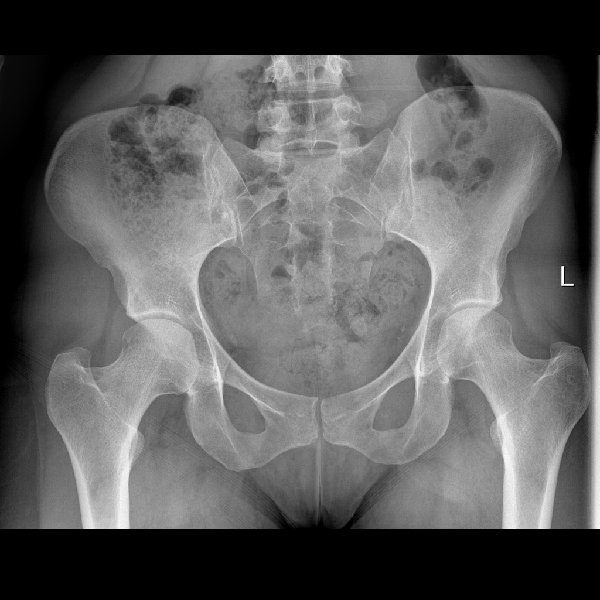

Learn the bony anatomy then test yourself